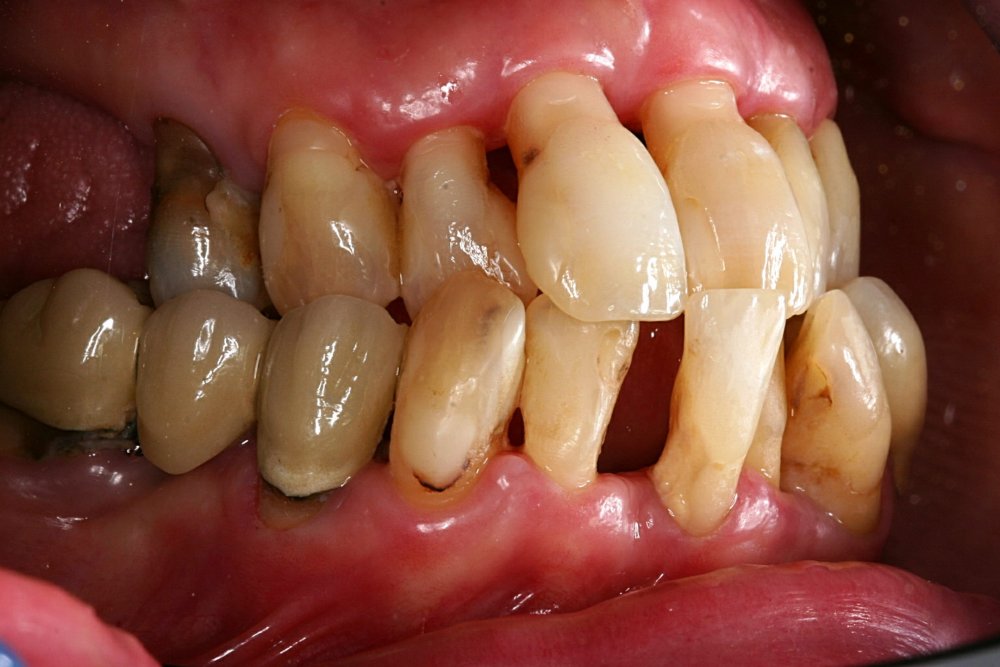

Qeyri-cərrahi parodontoloji müalicədən sonra bəzi hallarda, bu və ya digər bölgədə dərin parodontal ciblər (diş əti və sümük cibi) qalmaqda davam edir. Bu hallarda çox zaman müalicə cərrahi metodların tətbiqi ilə davam etdirilir. Bu zaman əsas məqsəd mövcud parodontal cibin bu və ya digər metodlarda aradan qaldırılmasını təmin etməkdir.

Çünki bu ciblər çox zaman pasiyent tərəfindən yetərincə təmizlənə bilmir. Bu isə həmin bölgəyə tədricən ərp və dolayısı ilə də bakteriya koloniyalarının toplanmasına səbəb olur. Bu proses yenidən yerli iltihabın ortaya çıxmasına səbəb olur. Tətbiq edilən cərrahi metodlar əsasən cibin yerləşdiyi diş bölgəsi, cibin eni, dərinliyi, konfiqurasiyası və s. xüsusiyyətlərə görə müəyyənləşdirilir. Bu zaman məqsəd mümkün olduqda həmin bölgədə bərpa prosedurunu həyata keçirmək, mümkün olmadıqda isə rezektiv müalicənin tətbiqi ilə həmin bölgəyə ərp toplanma ehtimalını azaltmaq və gigiyenik prosedurların icrasını pasiyent üçün rahatlaşdırmaqdır.